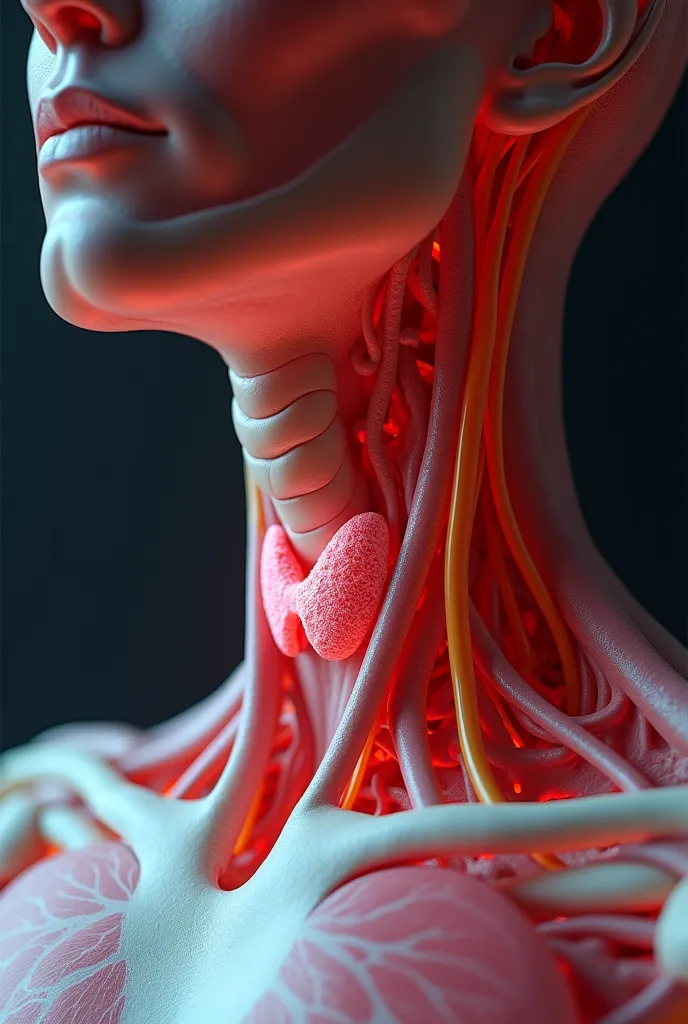

Pictures of swollen thyroid gland in neck, Use a Canon EOS 5D Mark IV with a 24

pictures of swollen thyroid gland in neck, Use a Canon EOS 5D Mark IV with a 24-70mm f/2.8 lens. Settings: ISO 100, aperture f/8, and shutter speed 1/125s to capture a sharp, vibrant image with a wide depth of field.

pictures of swollen thyroid gland in neck